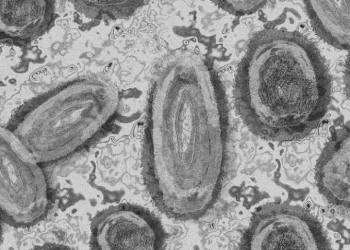

Photo by Fusion Medical Animation on Unsplash 백악관이 향후 2년 내에 오미크론과 같은 코로나19 변이 바이러스가 발생할 가능성이 있다는 전문가들의...